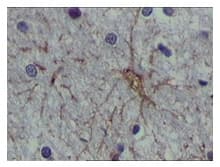

Mouse Monoclonal S10A1 antibody. Suitable for WB, IHC-P and reacts with Recombinant fragment - Human, Human samples. Immunogen corresponding to Recombinant Fragment Protein within Human Protein S100-A1.

Applications IHC-P, WB